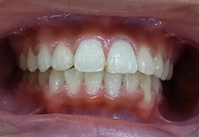

矯正治療前 矯正治療後

歯並びが悪いために 歯並びが綺麗になって

筋肉にまで影響が出ています。 筋肉の異常が無くなりました。

早期に治療を開始する事により骨格の変形を防ぐことが出来ました。